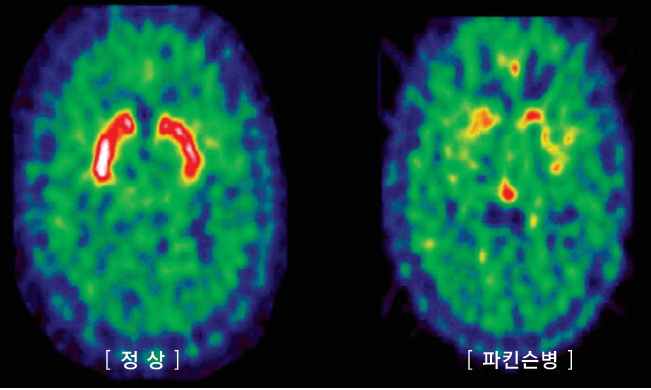

파킨슨병은 치매에 이어 두 번째로 흔한 퇴행성 뇌질환이다. 우리 뇌에는 여러 가지 신경 전달 물질이 있으며 그중 도파민은 운동에 필수적인 신경 전달 물질입니다. 파킨슨병은 중뇌의 흑질이라고 하는 뇌의 특정 부위에 있는 도파민을 분비하는 신경세포가 뚜렷한 이유 없이 점차 사라지면서 증상을 일으키는 질환이다.